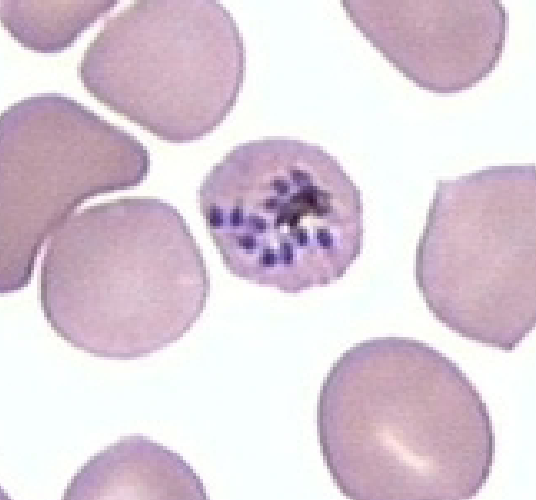

Plasmodium falciparum

Plasmodium falciparum

Plasmodium falciparum